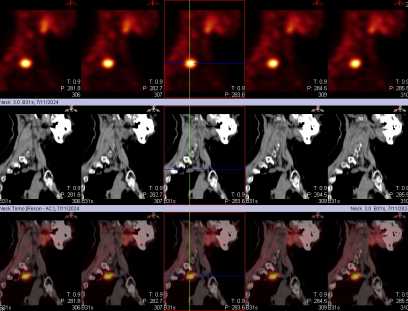

甲状旁腺显像异常图像(考虑甲状旁腺功能亢进):